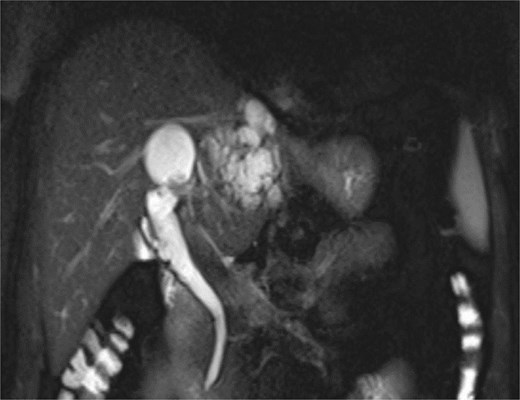

On clinical examination, mild tenderness in the upper abdomen was noted without jaundice or palpable masses. Laboratory investigations, including liver function tests, were within normal ranges, and no evidence of systemic infection was observed. Imaging studies using MRCP and CT demonstrated cystic dilatations of the intrahepatic bile ducts and a 5 cm hypodense lesion in the left hepatic lobe, raising suspicion for malignant transformation (Figs 1 and 2).

MRCP demonstrates multiple hyperintense, cystic lesions representing dilated intrahepatic bile ducts in the left hepatic lobe.